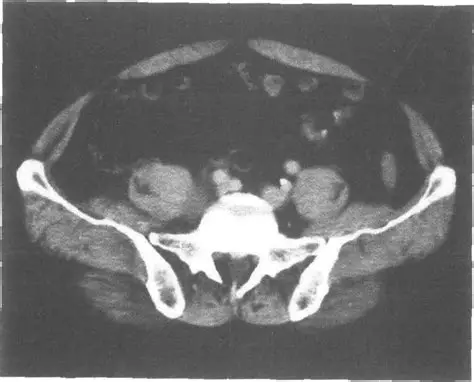

经耻骨联合上份横断层ct

层面第5腰椎下份层面骨盆 (女性,男性)x线大家期待的盆部ct影像图来啦